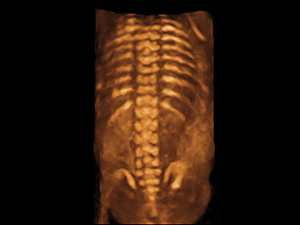

對例行結構性超聲波而言,二維(2D)超聲波已經足夠。三維(3D)及四維(4D)超聲波可說是錦上添花,有助加強孕婦及家人與小生命之間的連繫;大部份孕婦都樂於觀看胎兒3D/4D圖像。倘若經2D超聲波診斷出或懷 疑胎兒結構異常,3D或4D技術有助釐清及確定2D超聲波之診斷,有助孕婦及家人了解異常結構的情況。

懷孕二十週胎兒脊骨的三維圖像